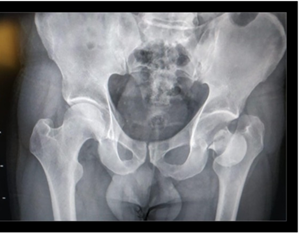

A los 18 meses de evolución, se constató un excelente resultado funcional de la cadera, sin dolor, trabajando en sus tareas habituales, y con recuperación casi completa de su alteración neurológica quedando con un déficit de dorsiflexión del pie de 10 grados. (figura 7)

Figura 7:  Radiografía de control de la prótesis cementada a los 18 meses